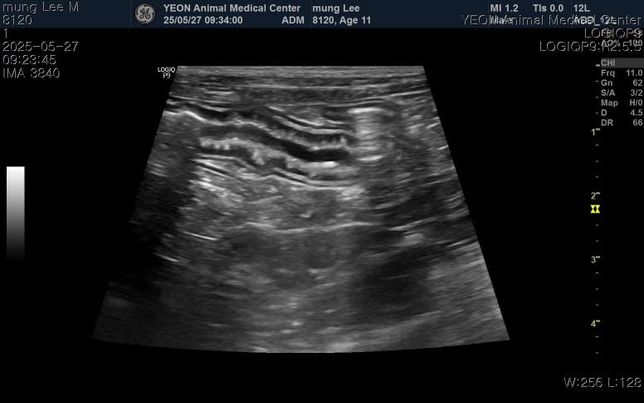

- 반려동물 건강반려동물매우진지한보더콜리강아지 담낭점액종 수술 없이 호전되기는 어려울까요?11살 4.7kg 포메 남아입니다.구토, 식욕저하, 기력저하로 내원해서 진료,검사 받아보니 염증, 간, 담낭 등 수치가 심하게 높다고 했고 빠른 입원치료와 담낭절제수술을 안내받았습니다.물만 먹어도 구토를해서 약도 못먹을것 같다하고.. 입원비와 수술비가 도저히 감당이 안될것 같은데 호전될 가능성이 전혀 없는걸까요?약물치료는 전혀 효과를 보지 못할까요?그리고 십이지장에 크론병?도 의심된다고 하는데 담낭 치료와는 치료방법이 상극이어서 담낭 먼저 제거하고 스테로이드치료가 필요하다고 안내받았습니다.자료 보시고 소견 말씀 부탁드립니다..1명의 전문가가 답변했어요